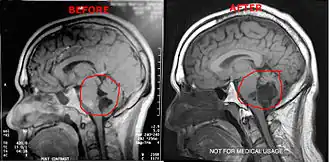

Diagnosis

Magnetic resonance imaging (MRI) and computed tomography (CT) brain scans can be used to identify these tumors.